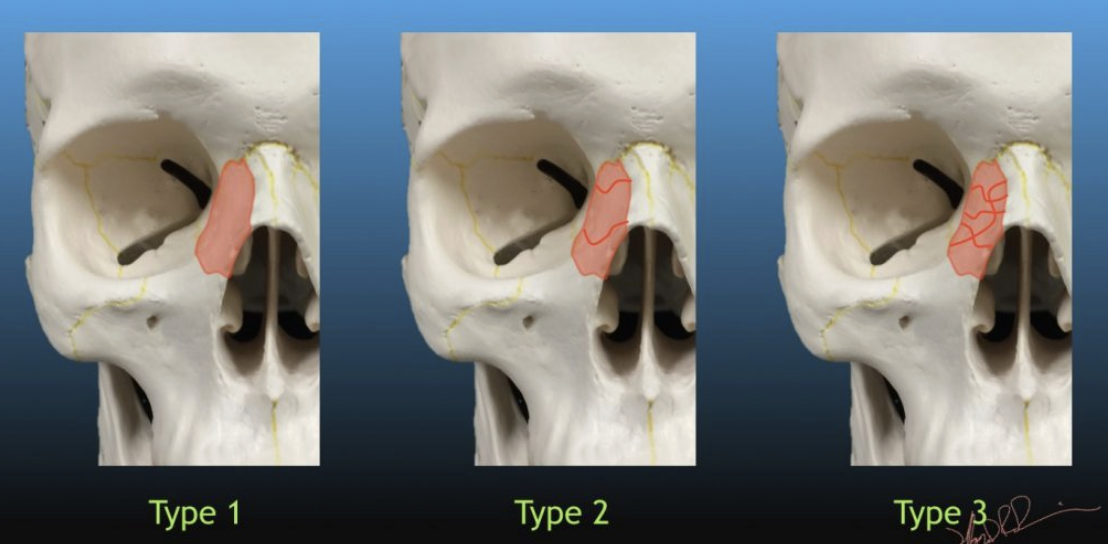

Que regarde-t-on ?

Une dissection carotidienne bilatérale avec une absence d’opacification carotidienne gauche.